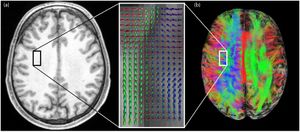

Publication: PLoS One. 2015 Oct 7;10(10):e0139434. PMID: 26444010 | PDF Authors: Tax CM, Chamberland M, van Stralen M, Viergever MA, Whittingstall K, Fortin D, Descoteaux M, Leemans A. Institution: Image Sciences Institute, University Medical Center Utrecht, Utrecht, The Netherlands. Background/Purpose: Fiber tractography plays an important role in exploring the architectural organization of fiber trajectories, both in fundamental neuroscience and in clinical applications. With the advent of diffusion MRI (dMRI) approaches that can also model "crossing fibers", the complexity of the fiber network as reconstructed with tractography has increased tremendously. Many pathways interdigitate and overlap, which hampers an unequivocal 3D visualization of the network and impedes an efficient study of its organization. We propose a novel fiber tractography visualization approach that interactively and selectively adapts the transparency rendering of fiber trajectories as a function of their orientation to enhance the visibility of the spatial context. More specifically, pathways that are oriented (locally or globally) along a user-specified opacity axis can be made more transparent or opaque. This substantially improves the 3D visualization of the fiber network and the exploration of tissue configurations that would otherwise be largely covered by other pathways. We present examples of fiber bundle extraction and neurosurgical planning cases where the added benefit of our new visualization scheme is demonstrated over conventional fiber visualization approaches. Funding: